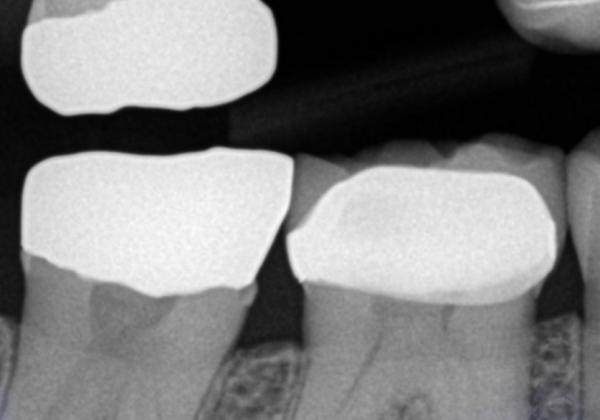

Omnicam and Posterior e.max Restorations

The CEREC software virutal design steps for both the CEREC AC and Omnicam virtual die are the same.  However, the colored virtual die does add more flavor to the process.  Our CADStar Mastering Posterior CEREC Applications class will teach both Omnicam or CEREC Blucam using the latest CEREC software.  The steps for planning, virtual design steps, and post mill finishing steps are the same.